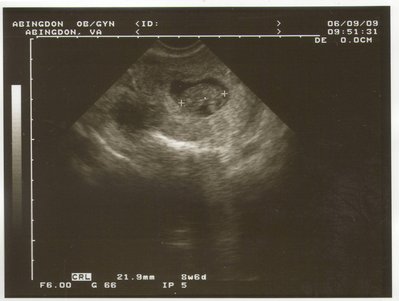

Татиана писал(а): Ой, ну как сказать: когда я своего ребенка увидела в 8 недель с ручками и ножками и сердебиением-то рыдала. А в 17- я уже делала 3д фотки: там человечек с личиком и щечками. Мне даже было страшно подумать, если что пойдет не так. в 8 недель? у меня, наверное, нет воображения совершенно... мож, поэтому и не рыдала Natiii, махнемся? я так мальччика хотела, а УЗИ показало девочку.

| Вложения: |

BabysFirstPic.JPG [ 316.26 КБ | Просмотров: 2429 ]

Похоже, и у меня воображение отсутствует  Я вот тоже удивилась, как в 8 недель Татьяна ручки-ножки умудрилась рассмотреть  Мы в 8 недель делали - да, серцебиение увидели, но никакие части тела и близко определить невозможно было... на этом сроке размер плода не больше 2 см. Ань, а эта фотка на каком сроке?

Хочу поделится фото моего малыша! Удивительно- он говорит ХАЙ всему миру. 13 недель срока